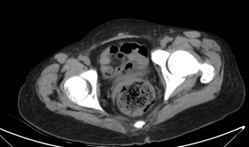

入院后请消化科、神经内科、眼科会诊,建议完善感染学指标,腹部增强CT,自身免疫性抗体谱,肌电图等。检查结果示自身免疫性肝炎及结缔组织病相关检测阴性。胸+全腹(含盆腔)CT平扫(图C-D):支气管炎,双肺多发炎性、纤维灶,建议随诊;双侧胸腔积液;左肩背部皮下结节,考虑良性病变,请结合临床;考虑食道裂孔疝,胃术后改变,请结合临床;胰头部饱满,建议随诊或进一步检查;脾大;双肾体积缩小、密度增高,所见骨质密度弥漫性增高,腹壁多发钙化灶,请结合临床;盆腔少量积液。眼超声:基本正常。

C

D